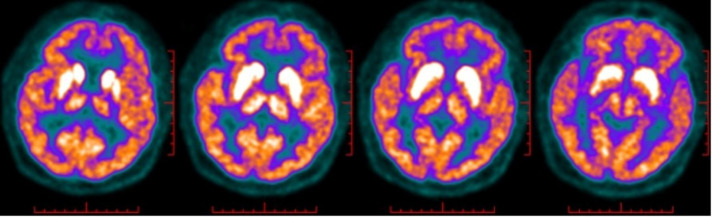

Results: All four patients exhibited signs of limbic encephalitis, including short-term memory deficits, seizures and psychiatric disturbances. Two cases also presented with faciobrachial dystonic seizures. MRI findings revealed hyperintense basal ganglia lesions in two patients. Treatment with corticosteroids, intravenous immunoglobulin and mycophenolate mofetil led to significant improvement in three patients, with no relapses during a follow-up period ranging from 33 to 60 months. One patient succumbed to pneumonia despite initial improvement of neurological function.